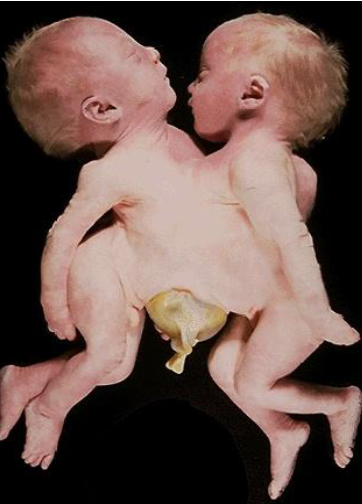

blood supply of twins becomes connected, allowing the movement of blood from one twin to the other across the placenta (monochorionic), causing circulation imbalance

define twin twin transfusion syndrome

recipient → heart failure

donor → anemia and renal failure

COD of death in twin-twin transfusion syndrome